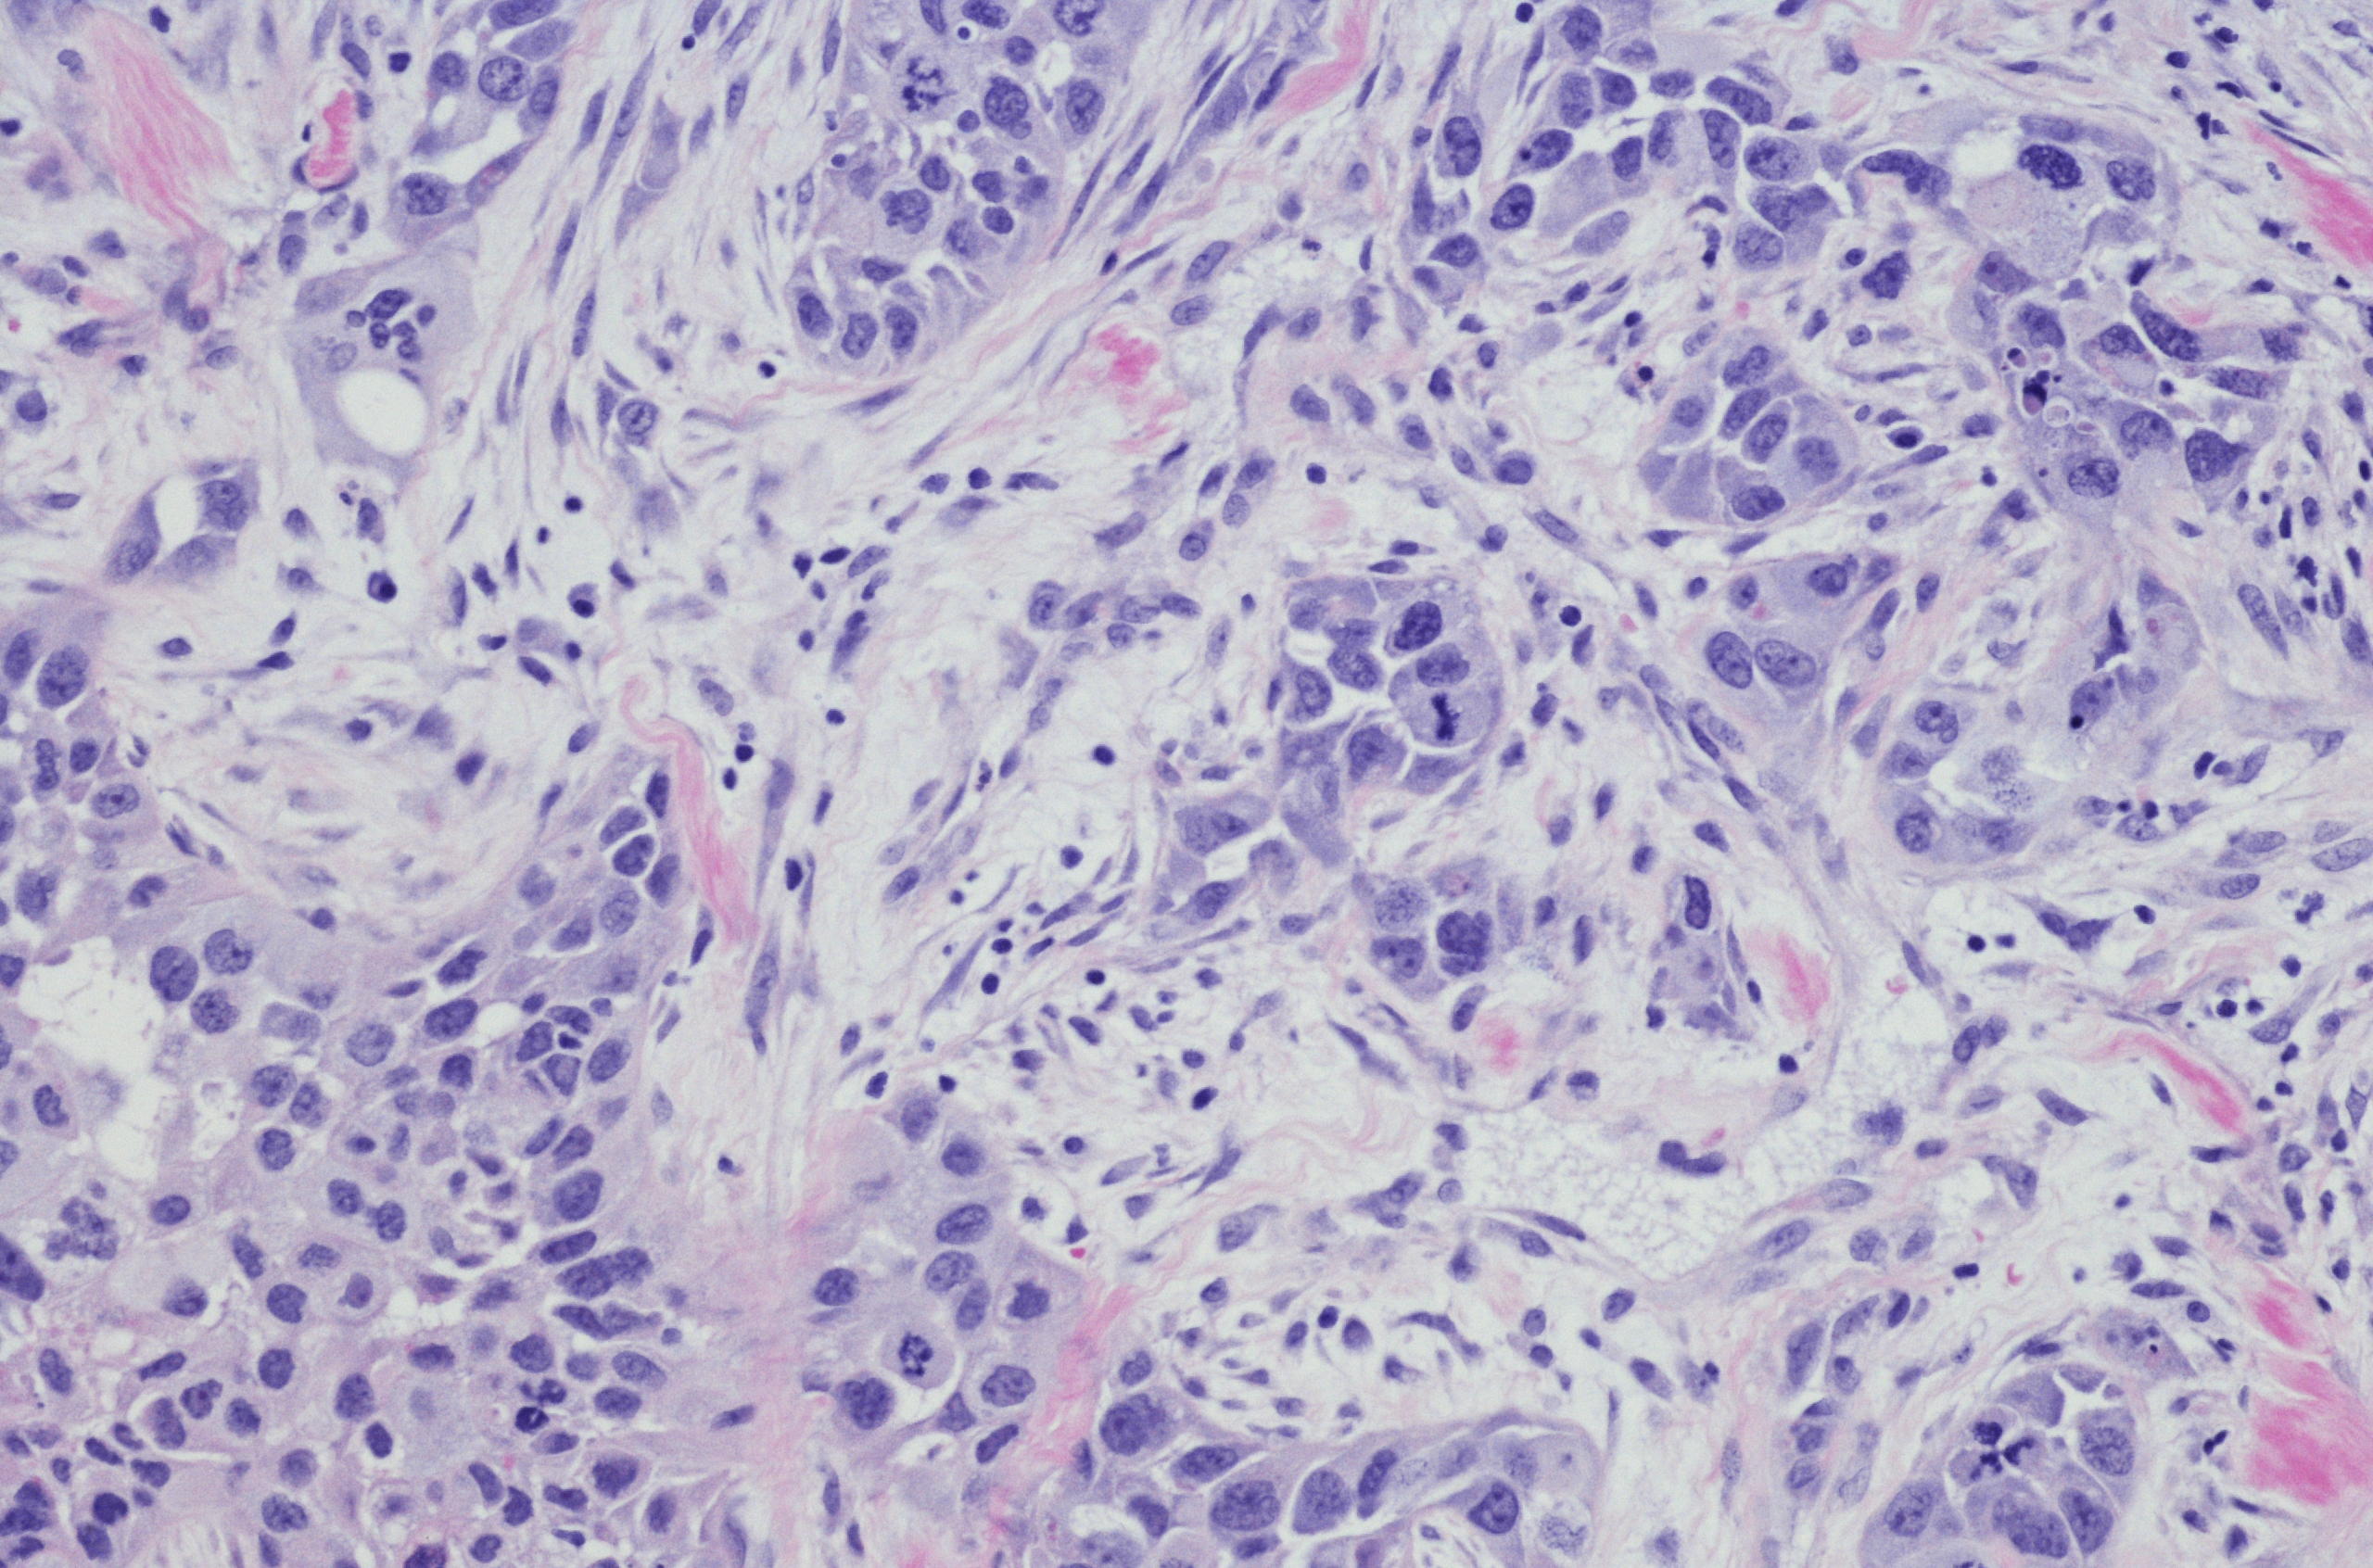

The term ‘triple negative’ is used to describe a type of breast cancer that does not have any of the three receptors commonly found on breast cancer cells. These receptors are:

Because of its triple negative status (Oestrogen Receptor negative, Progesterone Receptor negative and Human Epidermal Growth Factor Receptor 2 negative) this cancer type generally does not respond to receptor targeted treatments.

Depending on the stage of its diagnosis, Triple Negative Breast Cancer can be particularly aggressive, and more likely to recur than other subtypes of breast cancer.